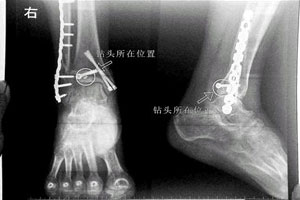

Patient claims doctor left drill bit in bone

A woman who claims a doctor left a drill bit in the bone of her right foot during surgery is asking for 120,000 yuan ($19,300) in compensation from a hospital, Beijing Youth Daily reported on Monday. The 48-year-old woman, surnamed Hu, broke her right ankle in a fall in March 2013 and was sent to You'anmen Hospital for surgery.